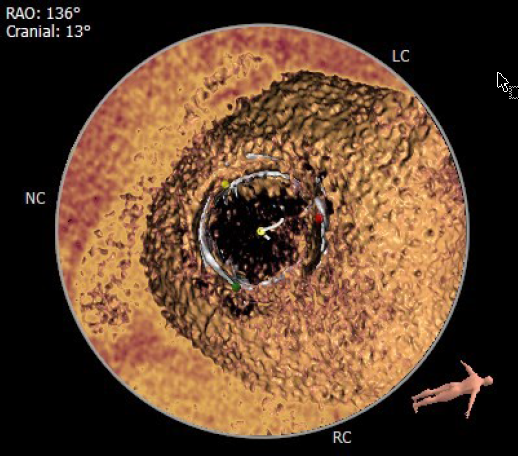

术中影像监护与评估(DSA&TEE)

原生物瓣少量反流

过瓣流增快,呈“五彩状”